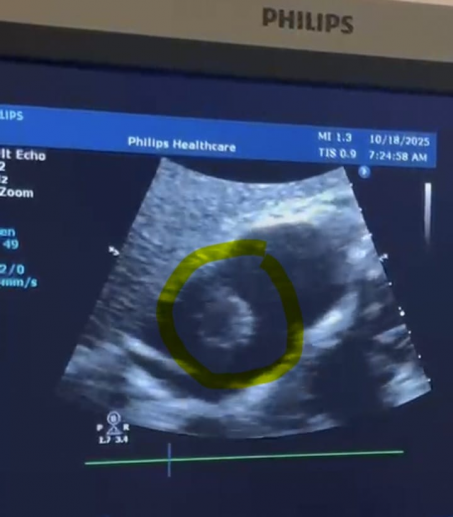

استقبلت مستشفى النجف الأشرف التعليمي

مريضة خمسينية ،تعاني من ضيق شديد في التنفس وتراكم السوائل منذ عامين.

وذكر اعلام

صحة النجف :" ان فحص الإيكو

القلبي اظهر وجود كتلة غير طبيعية داخل

القلب مصحوبة بانصباب تأموري متوسط. وعلى ضوء ذلك، تم نقل المريضة على وجه السرعة